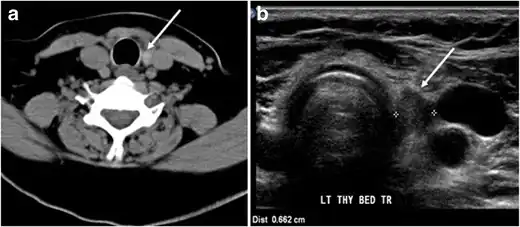

- Fig. 7. A 51-year-old female patient post total thyroidectomy for PTC with elevated thyroglobulin measurement. an Axial non-enhanced CT scan of the neck at the level of the thyroid bed demonstrates a well-defined, rounded, homogenously dense soft tissue situated between the trachea and left internal jugular vein (white arrow). b Transverse ultrasound image of the neck demonstrates a well-defined, homogeneous, hypoechoic soft tissue nodule measuring 6 mm (white arrow) with no detected micro-calcifications. Biopsy showed a predominantly residual normal thyroid tissue with micro-foci of PTC.[1]